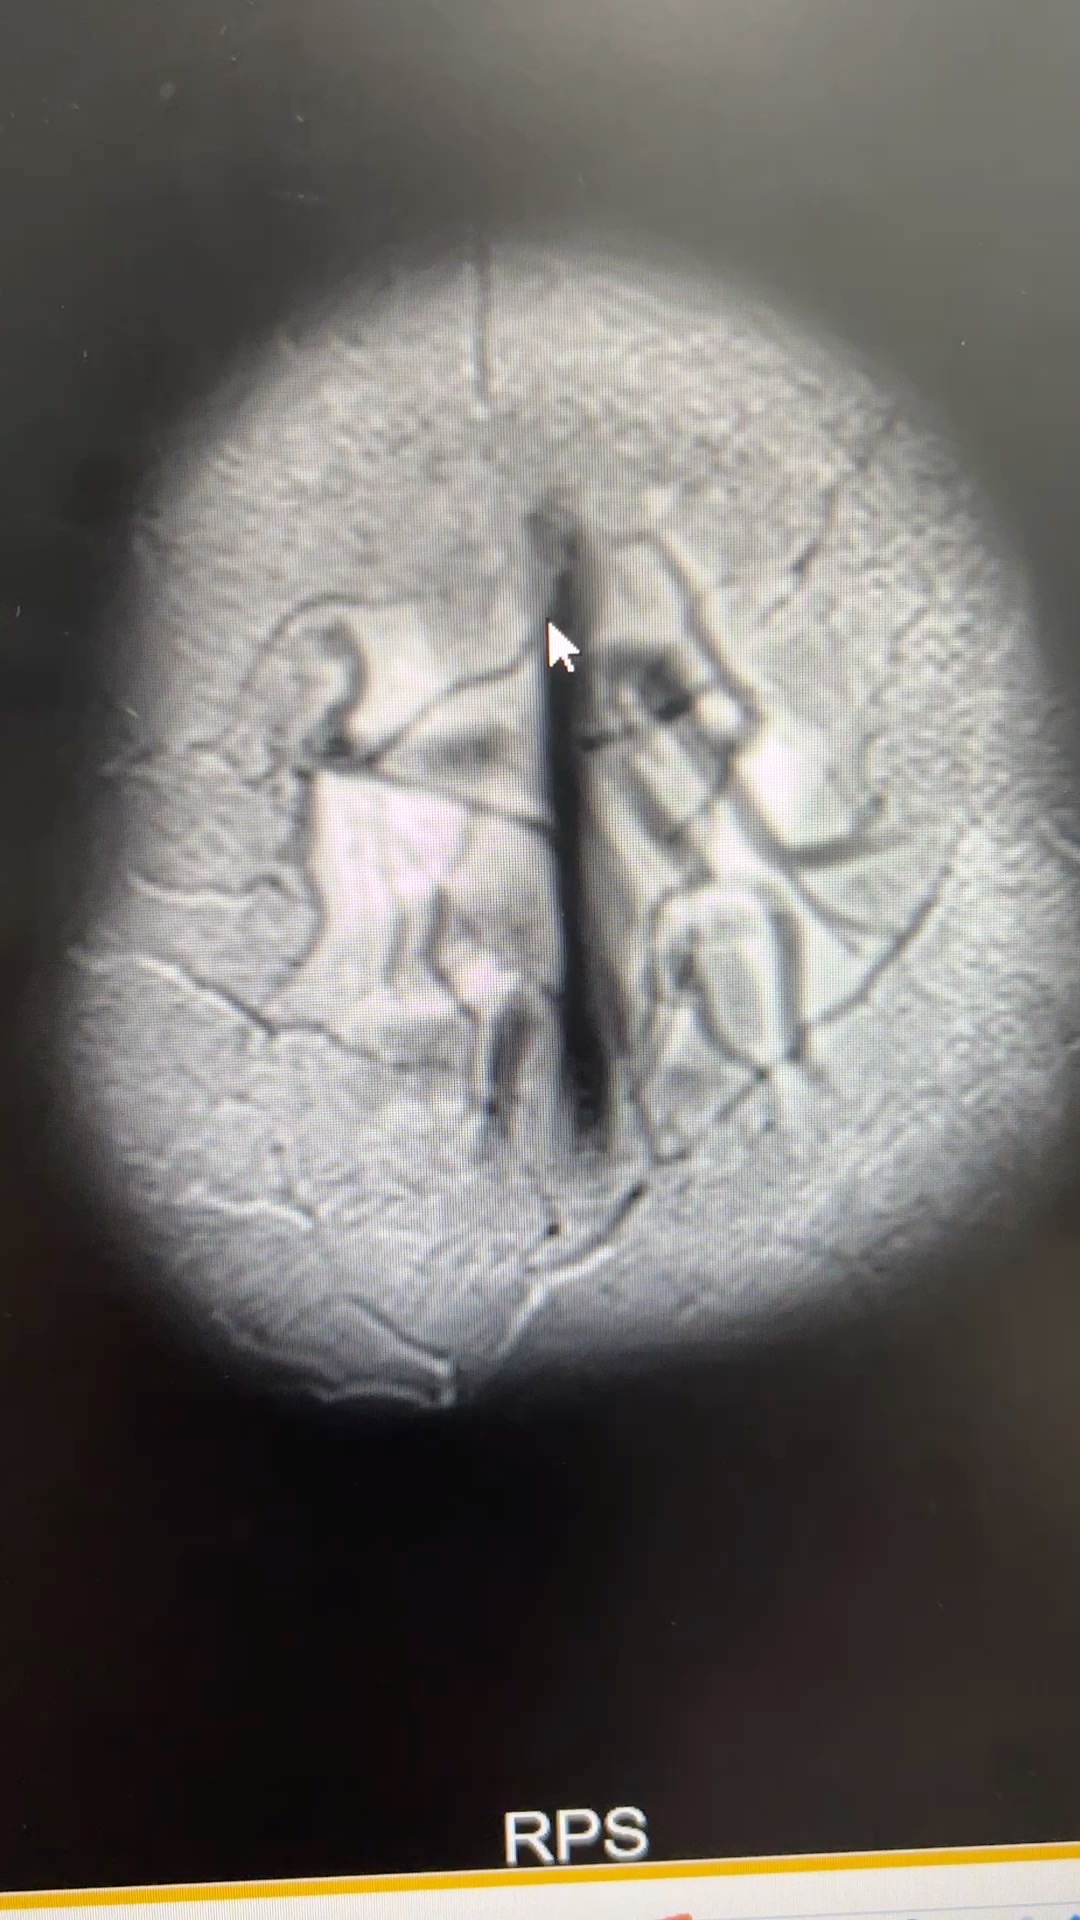

肢体无力半年,考虑什么?

患者,女,35岁,因“肢体无力半年”入院。

患者半年前无明显诱因出现左侧肢体无力,持续3天后自行好转。后出现行走后双下肢沉重无力,休息可缓解。1月前症状加重,上楼梯、蹲下起立困难,伴下肢肌肉酸胀,无皮疹,无二便改变,无晨轻暮重,至当地医院腰椎MR.I轻度退行性变,子“地奥司明、艾瑞昔步”口服,症状无改善。为求进一步诊治,拟“肢体无力”收治入院。

查体:神清,精神可,痉挛步态,言语清晰,对答切题,双眼眼球各向活动到边,双侧瞳孔等大等圆,直径3mm,对光灵敏,伸舌居中,双侧鼻唇沟对称,抬头肌力4级,双上肢肌力5级,右下肢肌力近端3+级,远端4级,左下肢肌力近端4级,远端5级,四肢腱反射亢进++++,双下肢肌张力增高,深浅感觉无增减。双侧指鼻不准,轮替慢,左侧明显,跟膝胫不准,闭目难立征阳性。霍夫曼征阴性,髌阵挛、踝阵挛阳性,双巴氏征阳性。